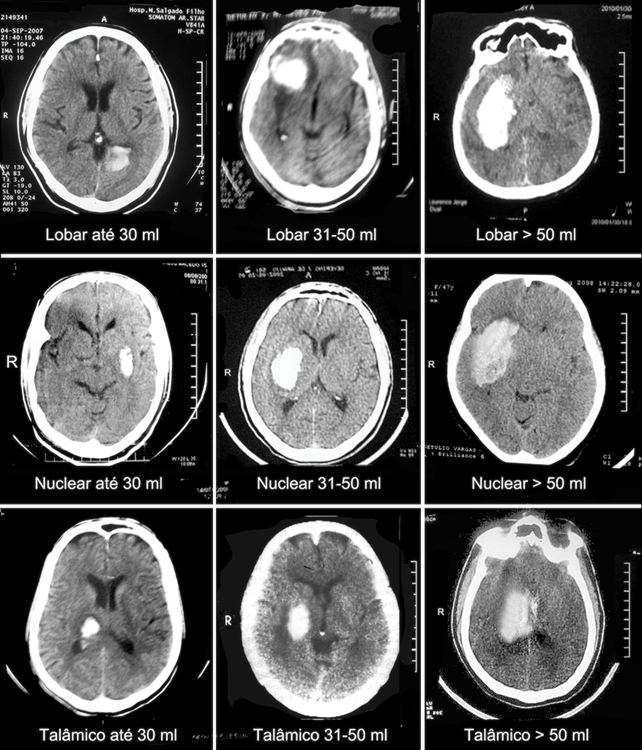

As for the clinical-neurological picture, the main findings were Motor deficit in 46% of patients (n=245), lowered level of consciousness in 38% (n=201), 17% with GCS-P between 09-12 (n=92), 18% with GCS-P 04-08 (n=93) and 3% with GCS-P ≤ 3 (n = 16). Regarding the distribution of cases according to the topography of the PICH we observed that they had hemoventricular 40% of patients (n=212), lobar lesions 34% patients (n=183), lesions in deep base nucleus topography 14% of patients (n=75) and thalamic hematomas 12% of patients (n=62). Regarding the volume of the lesions, on the other hand, the most observed range, in 49% of patients (n=263), was ≤ 30ml, followed by lesions between 31-50ml, in 25% of cases (n=148) and finally lesions ≥ 51ml in 23% of cases (n=121) (Table 2). Respective examples in Figure 1.

Figure 1 Examples of PICH extracted from the case series of this article, classified by skull CT, as to topography and volume of the lesion, except for ventricular lesions.